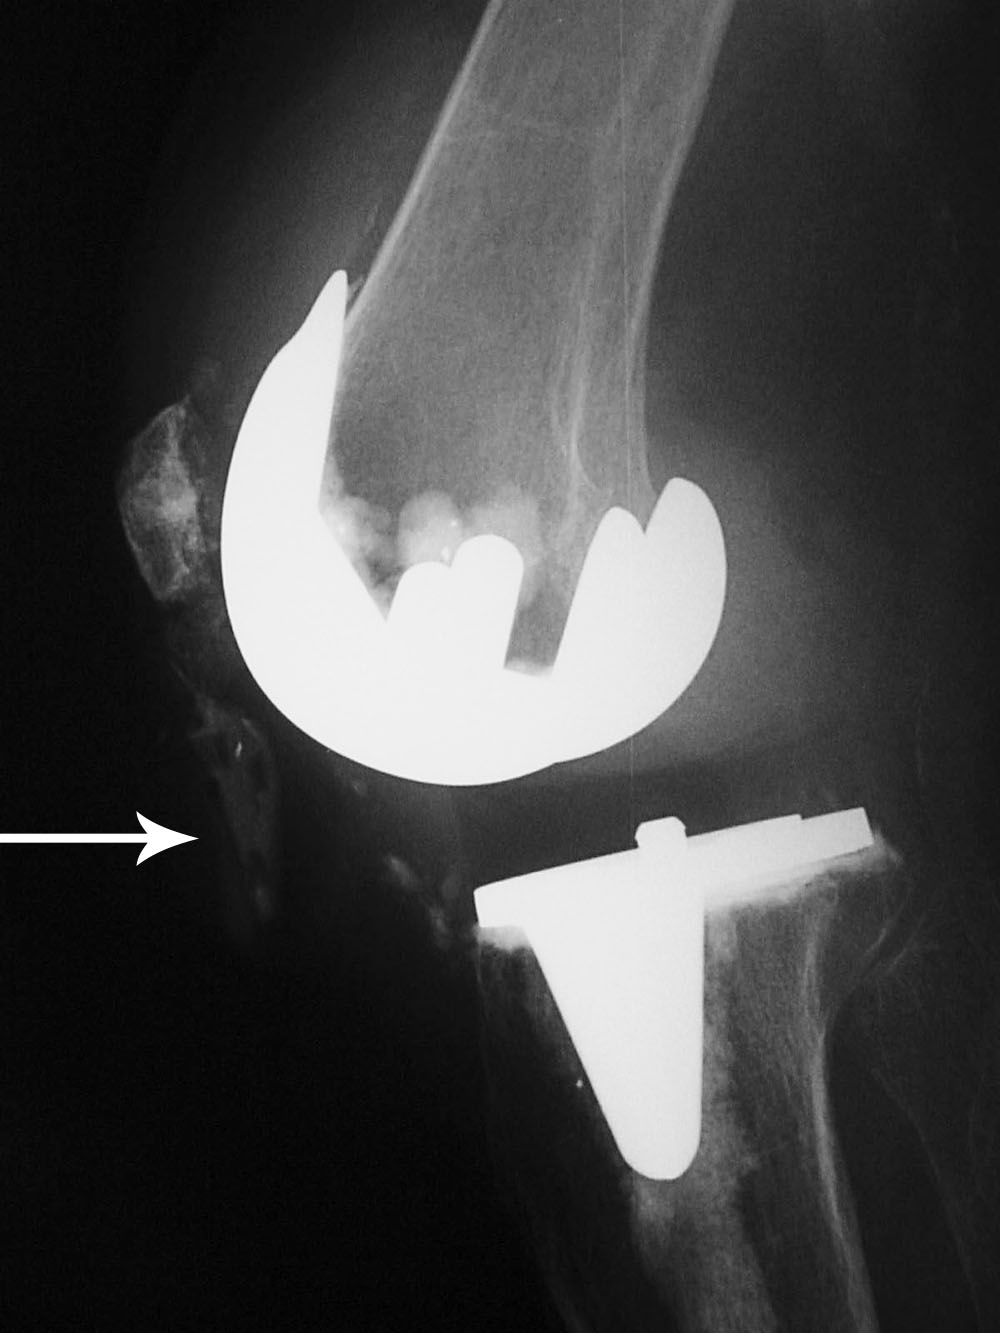

Rotating-hinge knee implants provide a mechanical linkage between the

femoral and tibial components and are used in

revision and tumor surgery when the bone and

soft tissues about the knee are severely damaged. These are highly constrained devices (figure: rotating-hinge knee implant; figure: rotating-hinge knee implant with failure). The tibial and femoral components are linked via a hinge which considerably limits varus-valgus and translational movement. The knee can only rotate approximately 10 degrees from flexion to extension (Mulcahy, 2013). Other variations on total knee arthroplasty designs have been introduced including a medial pivot knee design and a high flexion knee design.

Biomet Vanguard 360 Revision Knee System |

This replaced a loose prior total knee arthroplasty. The patellar button was left in place. A surgical drain is in place, and there is subcutaneous gas from the recent surgery. |